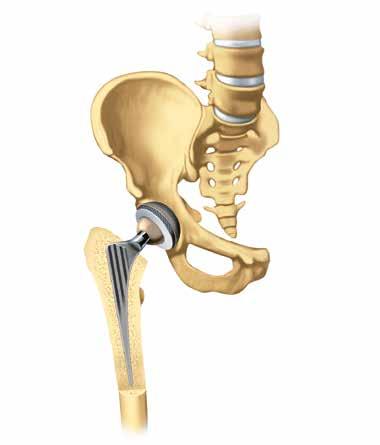

Sostituzione dell’articolazione

Se l’artrosi ha già danneggiato gravemente un’articolazione, impiantare una protesi può aiutare la persona colpita a ritrovare una qualità della vita che sembrava ormai perduta. È possibile ridurre e spesso perfino

eliminare i dolori e le limitazioni motorie, consen tendo alla persona colpita di riappropriarsi della propria autonomia.

Il termine tecnico con il quale si definisce una protesi articolare è «endoprotesi», dal prefisso greco «endo», che significa «interno». Un’endoprotesi è quindi un’articolazione artificiale che viene inserita all’interno del corpo, dove rimane per un lungo periodo di tempo per sostituire quella naturale.

Le endoprotesi utilizzate con maggiore frequenza sono quelle finalizzate a sostituire l’anca, il ginocchio e la spalla. In molti ospedali sono ormai entrate a far parte degli interventi di routine.

Un’articolazione artificiale è formata da diverse parti: la protesi è realizzata generalmente con leghe di cobalto-cromo o titanio, mentre gli elementi scorrevoli possono essere composti, ad esempio, da plastica polietilenica estremamente dura e ceramica. Prima di inserire l’impianto è necessario rimuovere la cartilagine danneggiata. Naturalmente, il chirurgo o la chirurga cercherà sempre di asportare solo la quantità di osso che è strettamente necessaria. In alcune articolazioni, ad esempio il ginocchio, è anche possibile utilizzare protesi parziali se la degenerazione interessa solo una porzione limitata della cartilagine.

Bacino

Acetabolo

Labbro acetabolare

Testa femorale

Collo femorale

Oggi la maggior parte delle protesi all’anca non è cementata. Il cemento osseo è invece utilizzato di norma per le protesi alle ginocchia.

Femore

Inlay per com ponente acetabolare

Componente testa femorale

Componente femorale